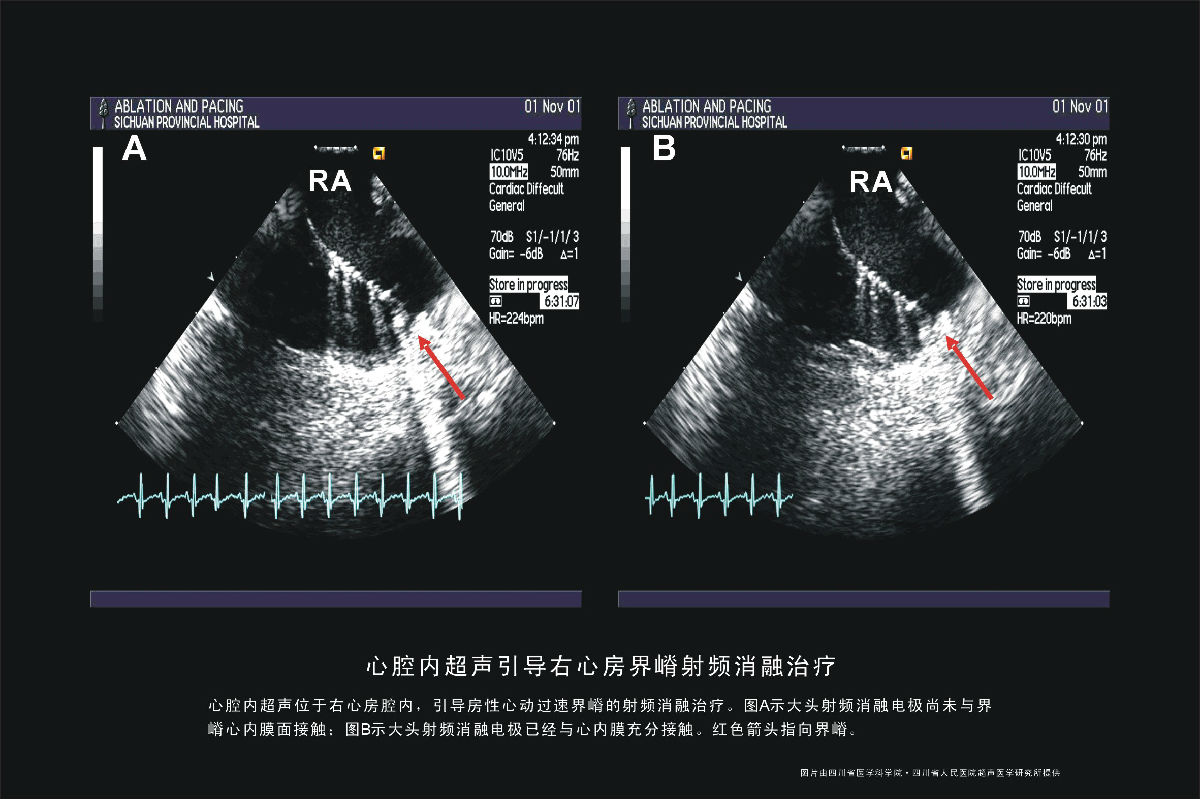

右心房界嵴射频消融